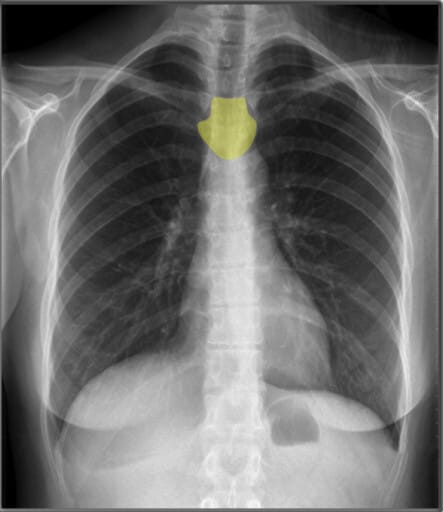

Landmarks in Chest X-ray (PA view)

폐와 심장 및 흉곽 구조물을 분석할 때 유용한 해부학적 지표로는 유방 음영(breast shadows), 심장 크기(cardio-thoracic ratio), 늑골횡격막각(costophrenic angles), 위 기포(gastric bubble) 등이 있습니다.

| 심장 크기 (Cardiac Width) |

| ✅ 정상적인 심장 크기는 흉곽 폭의 50% 이내여야 하며, 이를 심흉비(cardiothoracic ratio, CTR)라고 합니다. 비정상적으로 증가하면 심부전 또는 심장 비대의 가능성을 고려해야 합니다. |

| 대동맥궁 (Aortic Arch) |

| ✅ 좌측 폐문(hilus) 위에서 둥글게 보이며, 확장되거나 비대해지면 대동맥류 또는 고혈압성 변화 가능성을 고려해야 합니다. |

| 기관 (Trachea) |

| ✅ 정중앙에 위치해야 하며, 편위되어 있다면 종격동 이동(예: 무기폐, 기흉)을 의심해야 합니다. |